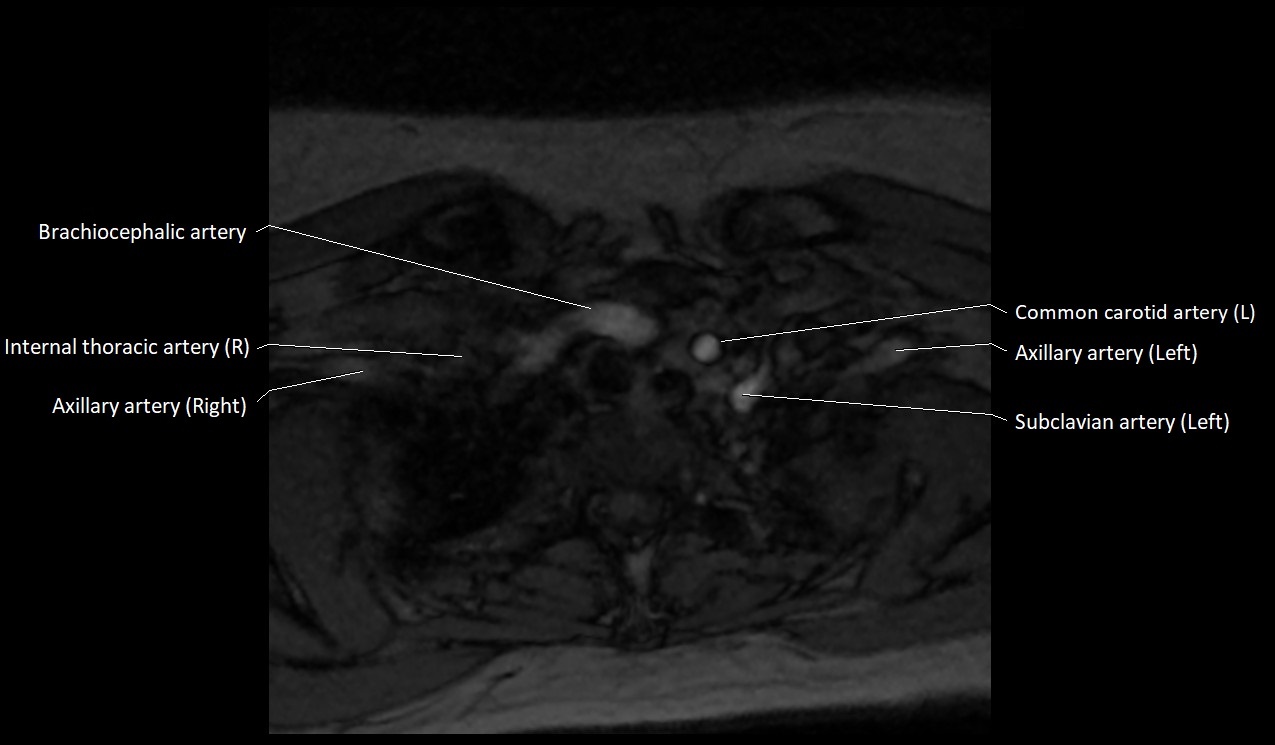

MRI images

image

CT image